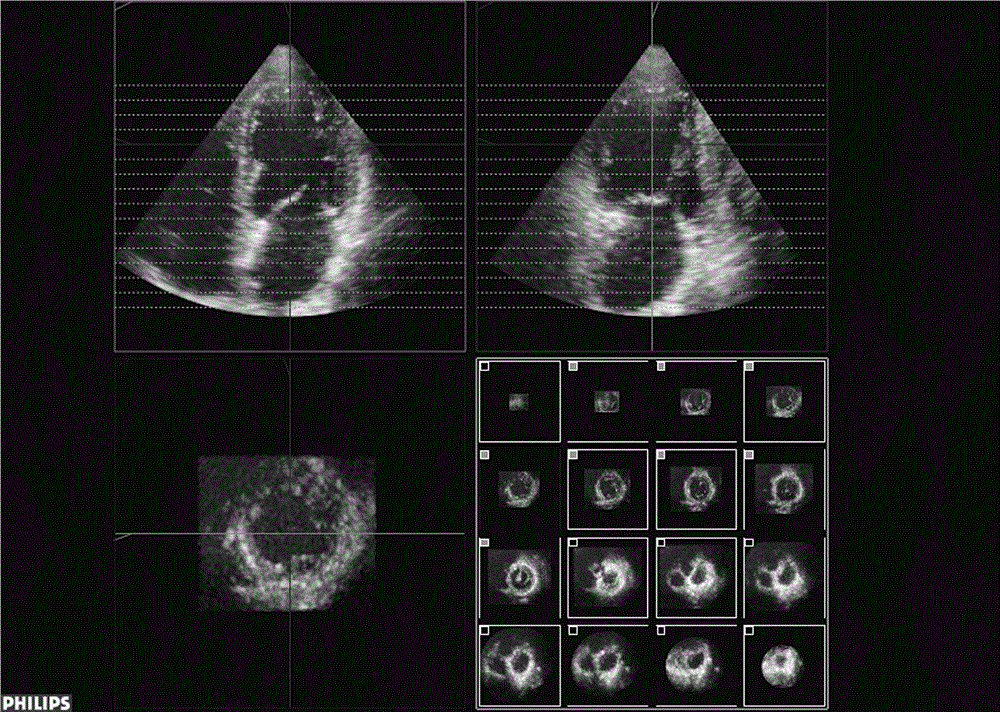

基于彩色多普勒3D成像的准静态心室-心脏磁场模型